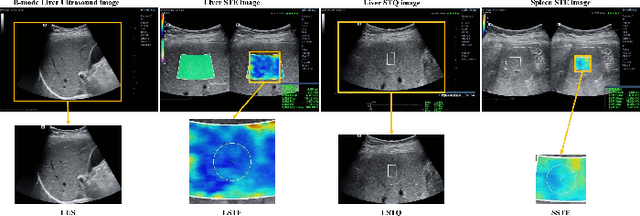

With the development of radiomics, noninvasive diagnosis like ultrasound (US) imaging plays a very important role in automatic liver fibrosis diagnosis (ALFD). Due to the noisy data, expensive annotations of US images, the application of Artificial Intelligence (AI) assisting approaches encounters a bottleneck. Besides, the use of mono-modal US data limits the further improve of the classification results. In this work, we innovatively propose a multi-modal fusion network with active learning (MMFN-AL) for ALFD to exploit the information of multiple modalities, eliminate the noisy data and reduce the annotation cost. Four image modalities including US and three types of shear wave elastography (SWEs) are exploited. A new dataset containing these modalities from 214 candidates is well-collected and pre-processed, with the labels obtained from the liver biopsy results. Experimental results show that our proposed method outperforms the state-of-the-art performance using less than 30% data, and by using only around 80% data, the proposed fusion network achieves high AUC 89.27% and accuracy 70.59%.